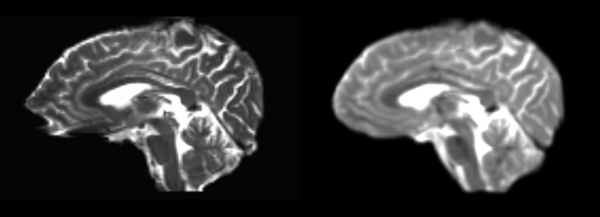

Rigid

- 53-t2 -> 31-t1 = rig1

- rig1 -> 53-t2 = rig2

Significant blurring, but every feature is in it's proper place.